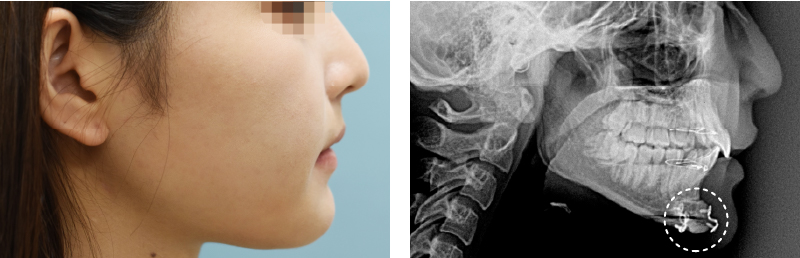

輪郭手術後のピン除去治療とは、顔面輪郭手術の際に使用した固定ピンやプレートを除去する施術です。輪郭手術で使用するピンやプレートは身体に安全な医療用の器具を使用しているため、本来であれば除去する必要はありませんが、「異物が体内に残るのが不安」「レントゲン撮影の際にピンやプレートが映ってバレるのを避けたい」といった理由で抜去を希望される方が一定数おられ、このような際に本施術が有効となります。当院で施術を行った方はもちろん、他院や海外(韓国など)で輪郭手術をされた方についても対応していますのでお気軽にご相談下さい。

なお、ピン除去手術は抜去にあたっての推奨期間があるため注意が必要です。具体的には、手術後にピン・プレートが骨や組織と完全に癒合する前となる、術後6か月後~1年(遅くとも2年)の間に施術を受けることをお勧めします。

輪郭手術で使用する固定具はいずれも医療用として認可されており、心臓手術や歯科治療などで日常的に使用している器具のため本来は抜去の必要はないのですが、患者様によっては「輪郭手術を行ったことをできるだけ周囲にバレないようにしたい」「レントゲン検査で金属が映らないようにしたい」という方もおられ、このような際にピン・プレート除去の手術を行っております。

- ピン除去を行う時期に特に決まりはありませんが、輪郭手術を行ってから抜去するまでの時間が長くなると、施術の際に使用したピンやプレートが骨に埋め込まれていくため手術の難易度がかなり高くなります。そのため当院では、固定ピン・プレートによって施術を行った部位の骨がしっかり接合されつつも、ピンなどが骨の中に沈み込む前となる術後6か月~12か月(遅くとも24か月以内)に施術を受けることをお勧めしています。個人差はありますが、顎先(オトガイ骨)は厚みがある頑丈な構造をしているため半年程度、頬骨は骨が薄く癒合までに時間が少しかかるため、1年程度で除去を行うとよいでしょう。

- 輪郭手術後のピン除去では両顎手術や頬骨整形の際に挿入した金属プレートやワイヤー、スクリューなどの固定具を除去することができるため、それ以降で行うレントゲン撮影などでは金属が一切映らなくなるというメリットがあります。出来るだけ手術をしたことをバレないようにしたい、また異物が体内に残っている状態に違和感があるという際には、ピン抜去手術が有効です。